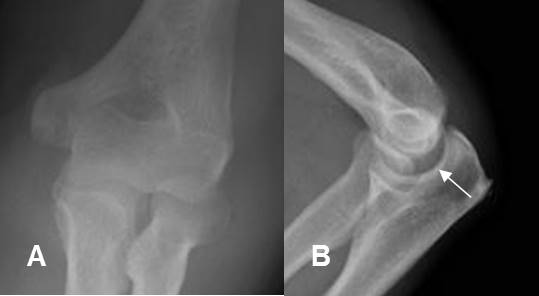

Fig 157. Luxación posterior del codo.

A: Rx AP y B: Rx lateral, que muestran luxación de las articulaciones ulnohumeral y radioulnar proximal.